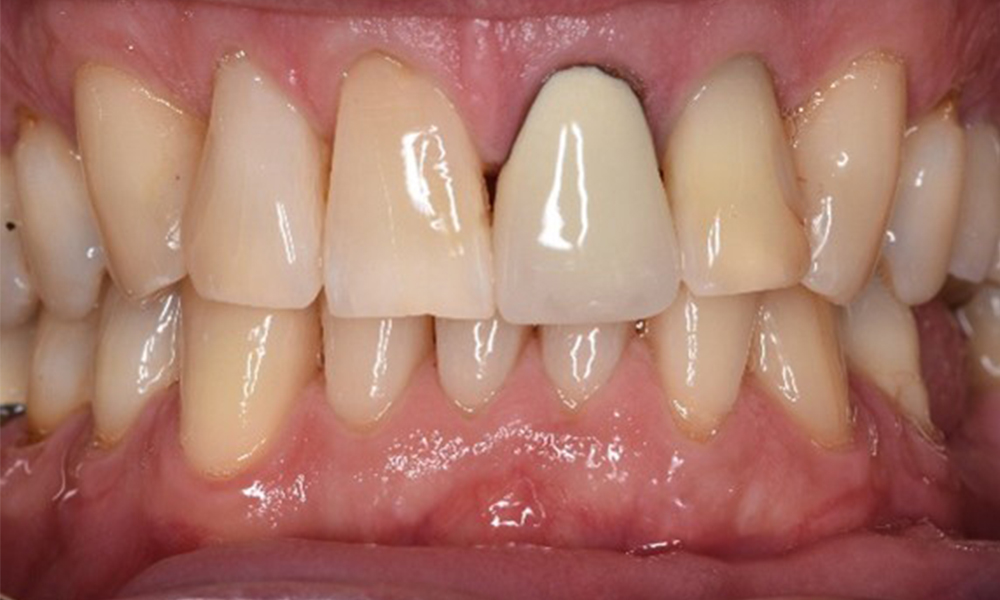

Der Patient hat einige zahnärztliche Restaurationen und zwei Implantate (2. und 4. Quadrant). Anhand der aktuellen Befunde lässt sich eine Gingivitis bei stabilem parodontalen Zustand am reduzierten Parodont (Stadium III, Grad A) feststellen.

Versorgungen: zahnärztliche Restaurationen (NEM keramisch verblendet), zwei Implantate (2., 4. Quadrant)